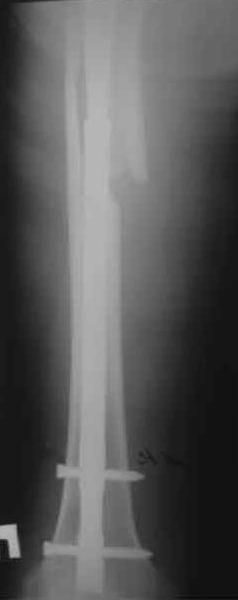

Re: Перипротезный перелом

Произведено закрытое удлинение ножки эндопротеза с помощью ретроградного интрамедуллярного стержня. Продолжительность операции 3 часа. Два из них закрытое восстановление длины бедра диистрактором

таз-бедро.